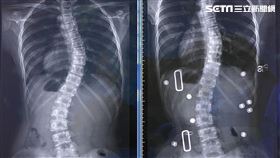

實境AR矯正脊椎側彎 27歲女長高3.7公分

27歲的蔡小姐罹患重度脊椎側彎,嚴重壓迫神經導致手抬...

2022/12/02 18:36